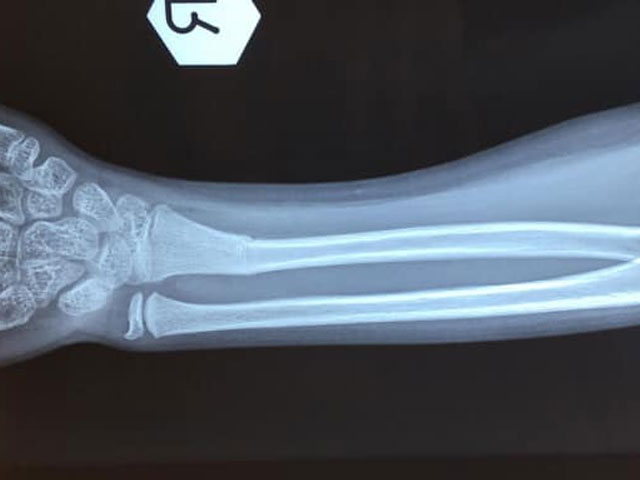

《小童前臂骨折》

小童的骨質軟而有彈性,不用很大外力就能折彎,因此稍一不慎在耍樂蹦跳期間跌倒或從稍高位置跌下就有可能造成骨折。

- 醫生會先以X光去確定受傷位置和骨折的嚴重程度

- 輕微骨折只需要以石膏固定約4個星期便可

- 若骨頭有斷裂、移位或變形的情況,則需要以手術方式處理

- 手術會先將骨折的地方復位,以鋼針固定後再輔以石膏加固。待骨折在術後約4-5星期愈合後,才把鋼針及石膏拆除

- 手術後的三個月內,應避免劇烈運動以慎防小朋友在同一位置受傷